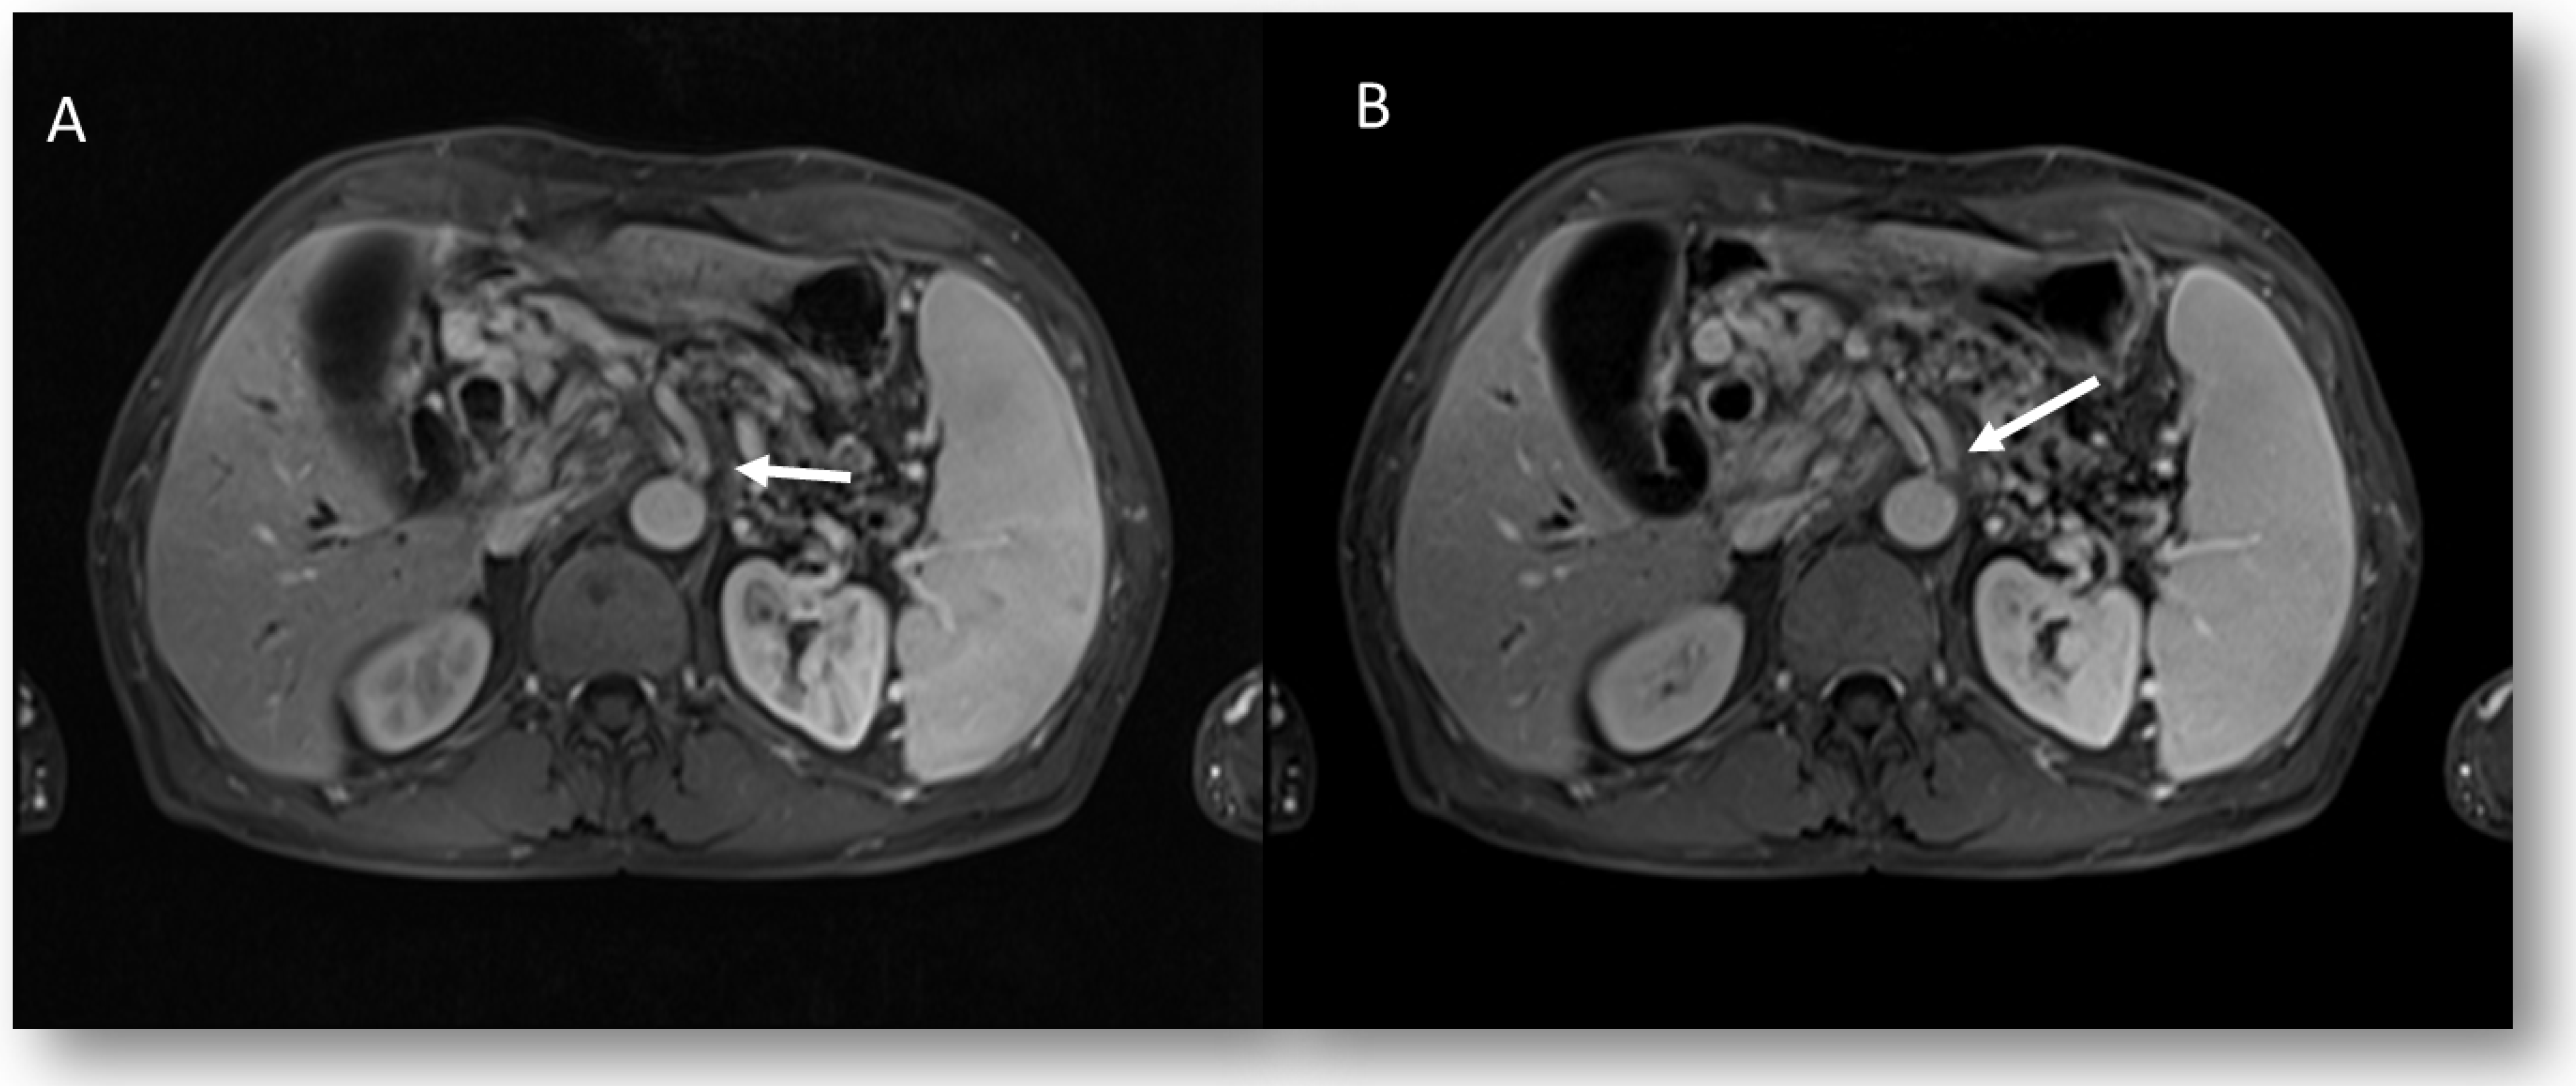

Figure 4. MRI assessment post n-CRT treatment: fibrotic response in T2-W axial (arrow) (A) and sagittal plane (arrow) (B).

At the second level, the report is based on the presence of a “findings” section, organized with subheadings. With this “structure”, it is possible to report all lesion-relevant data. For example, during MRI rectal cancer staging [65,66], the templates should report all the relevant issues on primary lesions and nodal status, such as the circumferential resection margin’s (CRM) involvement, extramural venous invasion (EMVI), and tumor deposits, in order to define the proper patient treatment. For MRI rectal cancer restaging, all relevant issues are re-assessed [65,66] to define the treatment response and the proper patient therapeutic approach (Figure 4), (i.e., total mesorectal excision, versus the “wait and watch” approach) [67,68,69,70,71,72,73,74].